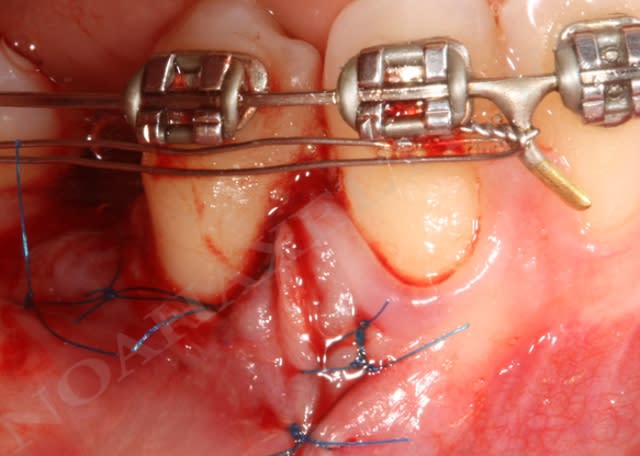

Img 8465 fqhxid - Eugenol

Initial ctkv65 - Eugenol

Lit receveur loll9i - Eugenol

Mise en place du greffon conjonctif ejn6xx - Eugenol

Sutures e7ixmz - Eugenol

Zone de prelevement palatin wngjgr - Eugenol